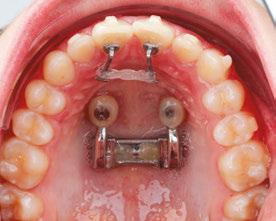

Drs. Claudia Pinter and Stanley Liu illustrate a protocol to improve nasal breathing in orthodontic care 31